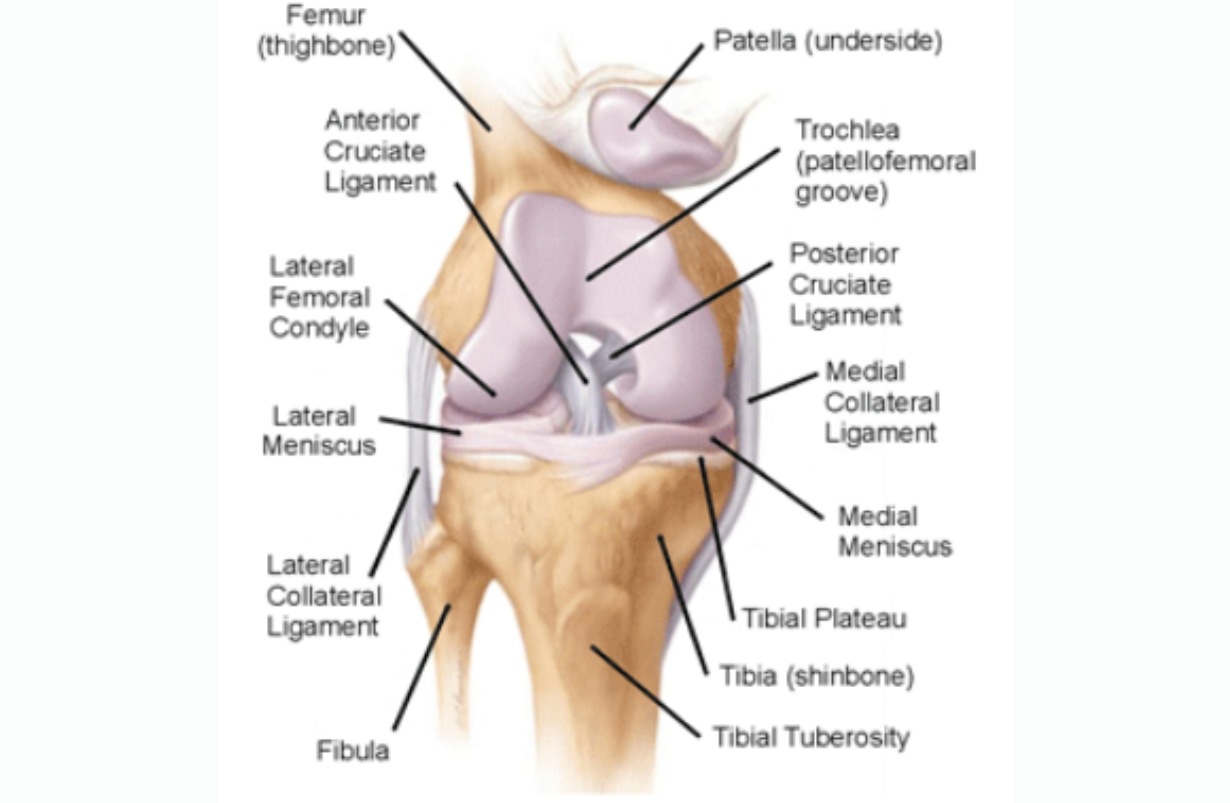

Anterior Cruciate Ligament Tear

The anterior cruciate ligament goes from the back of the femur to the front of the tibia, and keeps the shin from sliding forward.

Lateral Meniscal Tear

Tear in the outer cartilage of the knee that cushions the femur as it presses down on the tibial plateau, e.g., in walking. This typically occurs with twisting injuries of the knee. For example it could happen to the right knee if the leg were externally rotated, and a player were tackled from the right side. Radiograph from Wikipedia.

Medial Meniscal Tear

Tear in the inner cartilage of the knee that cushions the femur as it presses down on the tibial plateua, e.g., in walking. BENEFICIAL POSES: Dandasana, Vasisthasana, Paripurna Navasana, Ardha Navasana. EXPLANATION: These poses activate and strengthen the vastus lateralis, the most lateral of the four muscles that form the quadriceps. If it can be made to work more strongly, it will mildly tilt the femoral condyles laterally, away from the medial meniscus, REFERENCE: Kise NJ, Risberg MA, Stensrud S, Ranstam J, Engebretsen L, Roos EM. Exercise therapy versus arthroscopic partial meniscectomy for degenerative meniscal tear in middle aged patients: randomised controlled trial with two year follow-up. BMJ. 2016 Jul 20;354:i3740. doi: 10.1136/bmj.i3740.

Posterior Cruciate Ligament Tear

The posterior cruciate ligament goes from the front of the femur to the back of the tibial plateau, keeping the shin from sliding backwards. Injury often results in hyperextending the knee. BENEFICIAL POSES: Heel Sliding (see video), Janu Sirsasana, Supta Padangusthasana, Ardha Navasana, (later) Utkatasana. EXPLANATION: This uncommon injury occurs when the tibia is forced backwards, and therefore may be caused by a low tackle from the front or a fall. Treatment of most injuries is conservative: iNCREASING range of motion at the hip early, to take strain off of the knee, and strengthening later. Heel sliding maintains range of motion and coordinates ankle and hip motion with that of the knee. Strong hamstrings and quadriceps protect the healing ligament from further injury. These poses do exactly that, and should begin soon after the injury to avoid restricted range of motion later. Reference: Pierce CM1, O'Brien L, Griffin LW, Laprade RF. Posterior cruciate ligament tears: functional and postoperative rehabilitation.Knee Surg Sports Traumatol Arthrosc. 2013 May;21(5):1071-84. doi: 10.1007/s00167-012-1970-1. Epub 2012 Apr 8.